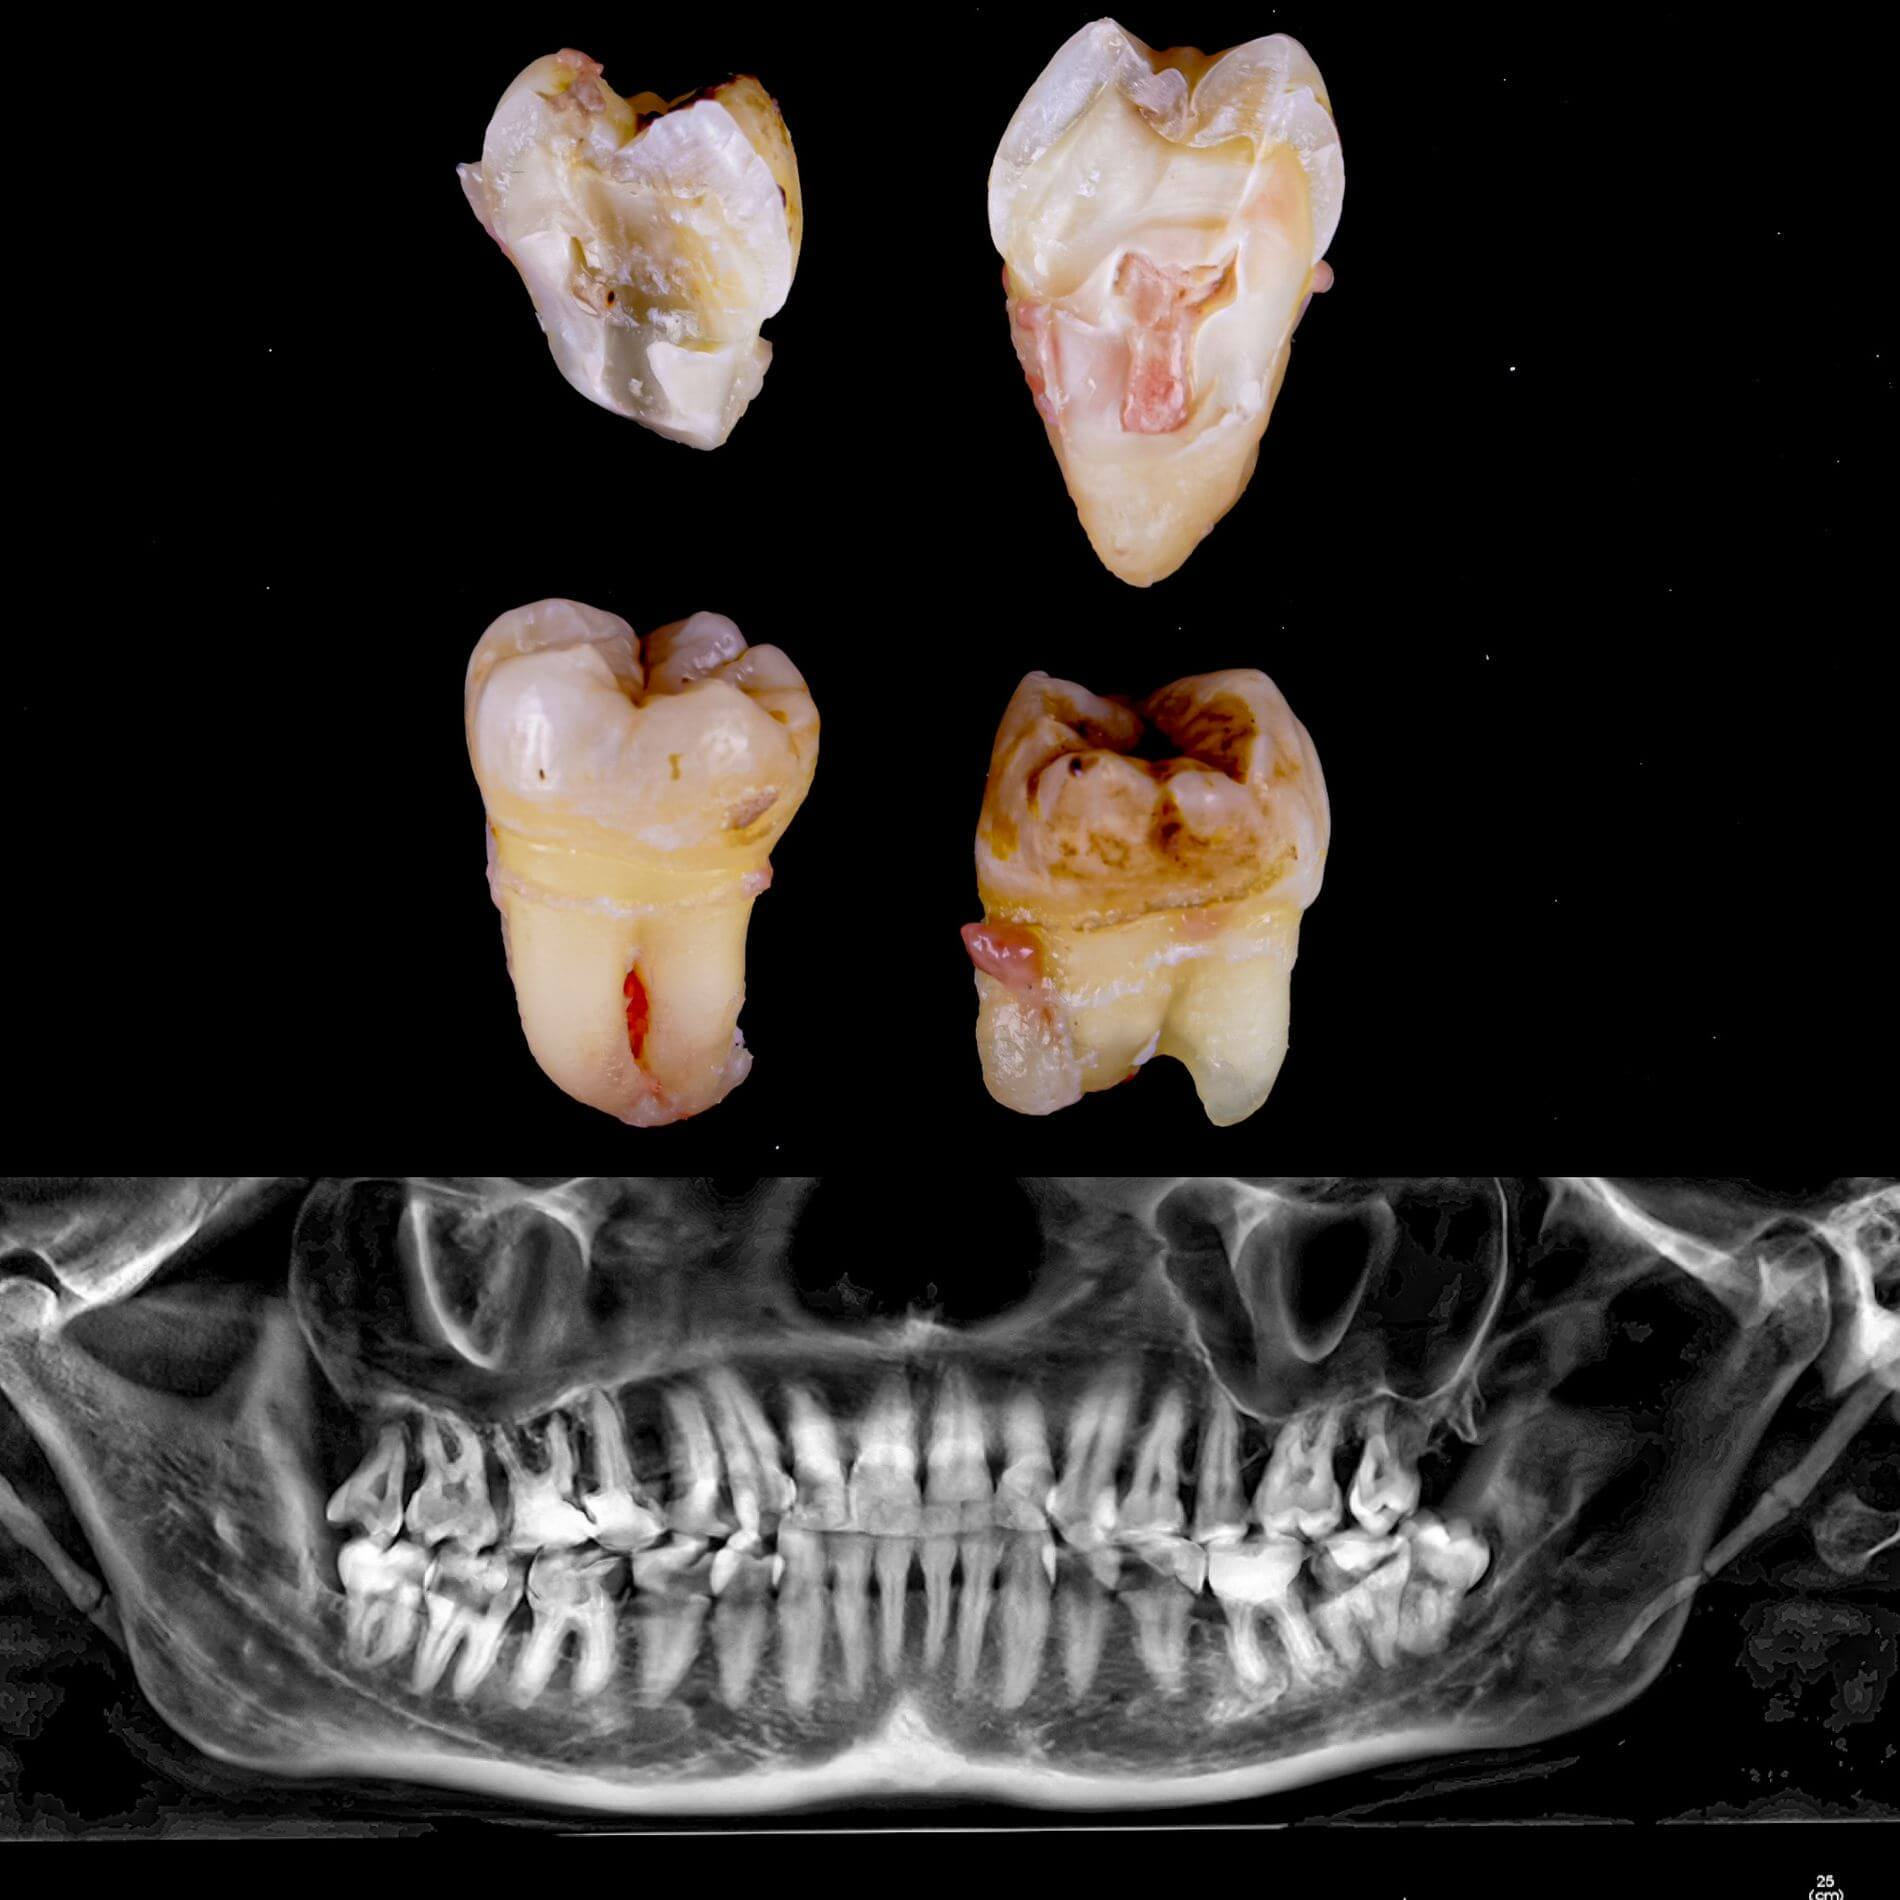

Виды удаления зубов мудрости

• Полное удаление зуба - если зуб полностью прорезался и имеет сросшиеся корни.

• Отдельное удаление коронки зуба и его корней - если зуб прорезан и корни растут по отдельности.

• Удаление зуба по схеме 1 или 2 с разрезом десен - если зуб прорезан частично.

• Разрез десен, освобождение зуба от близлежащей кости ультразвуком и удаление по схеме 1 или 2 - если зуб не прорезался, но беспокоит.

Галерея